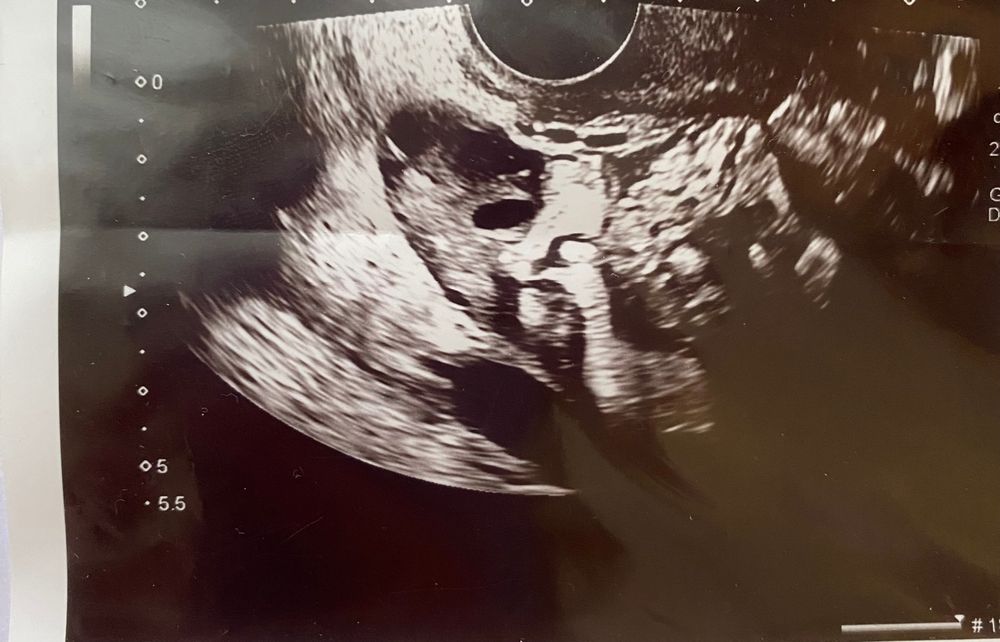

Девочки, кто разбирается в узи. Это может быть такой фолликул овальной формы?😬 там рядом есть еще и круглый. Такое у меня впервые…